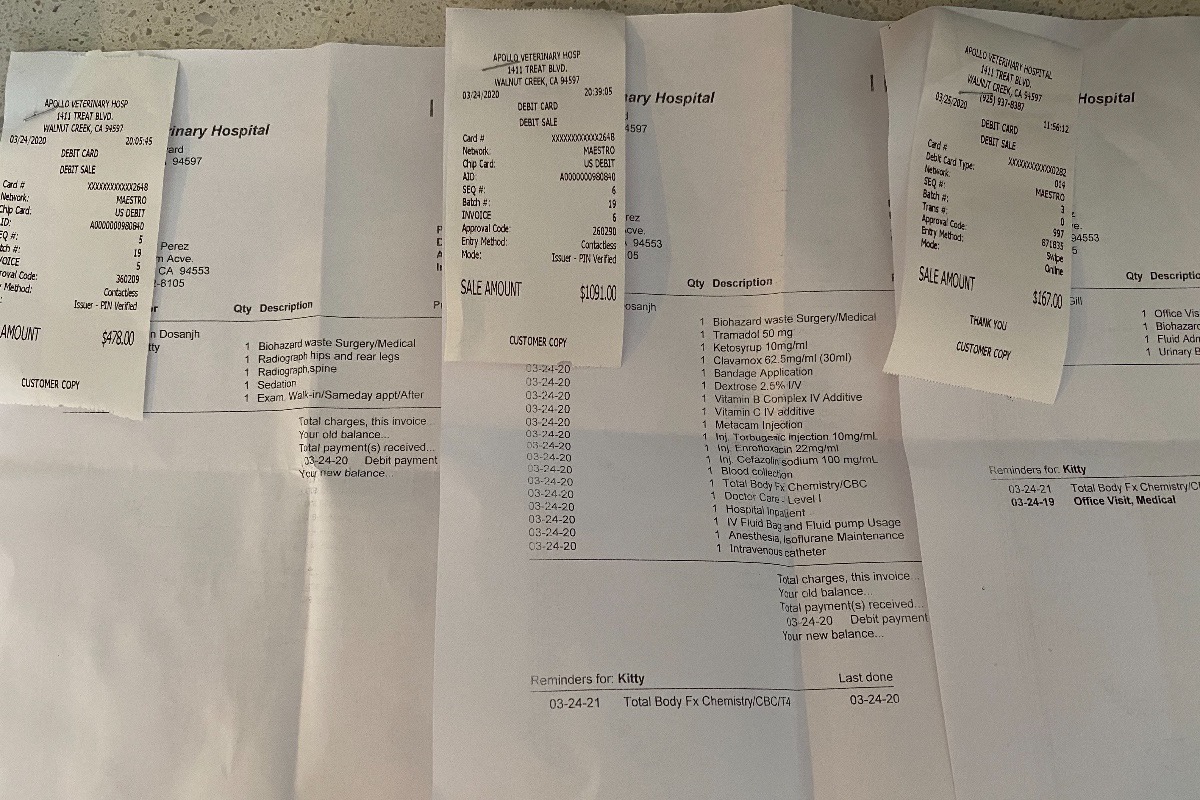

He had been hit by a car. Kitty was almost lifeless. his breath was shallow and deteriorating, his eyes were rolling while his left hind leg was dangling. I ran to my husband (who was giving our 19 month old twins a bath) we stealthy packed up the car and drove to the closest veterinarian hospital. The doctor sedated him to get x-rays and to relive the pain. After the X-rays his vitals were taken. His temperature had dropped so severely the vet urgently wrapped him up in heating blankets and hooked him up to fluids. Doc fed him some vitamins and glucose through the IV to keep him going. The radiography showed no visible signs of internal bleeding but the blood test told a different story. Although he wasn't bleeding internally, the diagnostic test showed that his liver and kidneys were struggling to preform from the impact of the car, not catastrophically enough for emergency surgery but enough to cause concern. He hasn't been able to urinate since and we've been taking him into the vet to relieve his bladder while we await surgery.

As for the X-ray results, we were informed that his femur had shattered into 7 pieces and that the trauma was too great to save his leg. Plating the leg would consist of multiple surgeries with subsequent physical therapy for months and even then there was no guarantee that he would actually be able to use the leg again. After consulting with one another, the orthopedic surgeons agreed that amputation would be the best bet and the most cost effective. Still a whopping 6,000 for the amputation. This doesn't include the overnight care, medication, check ups, or any other variable that may come into affect. This is on top of the 2,000 we have already spent just to diagnose the problem. Kitty is due to get his surgery Tuesday March 31st, one week after this tragic accident.